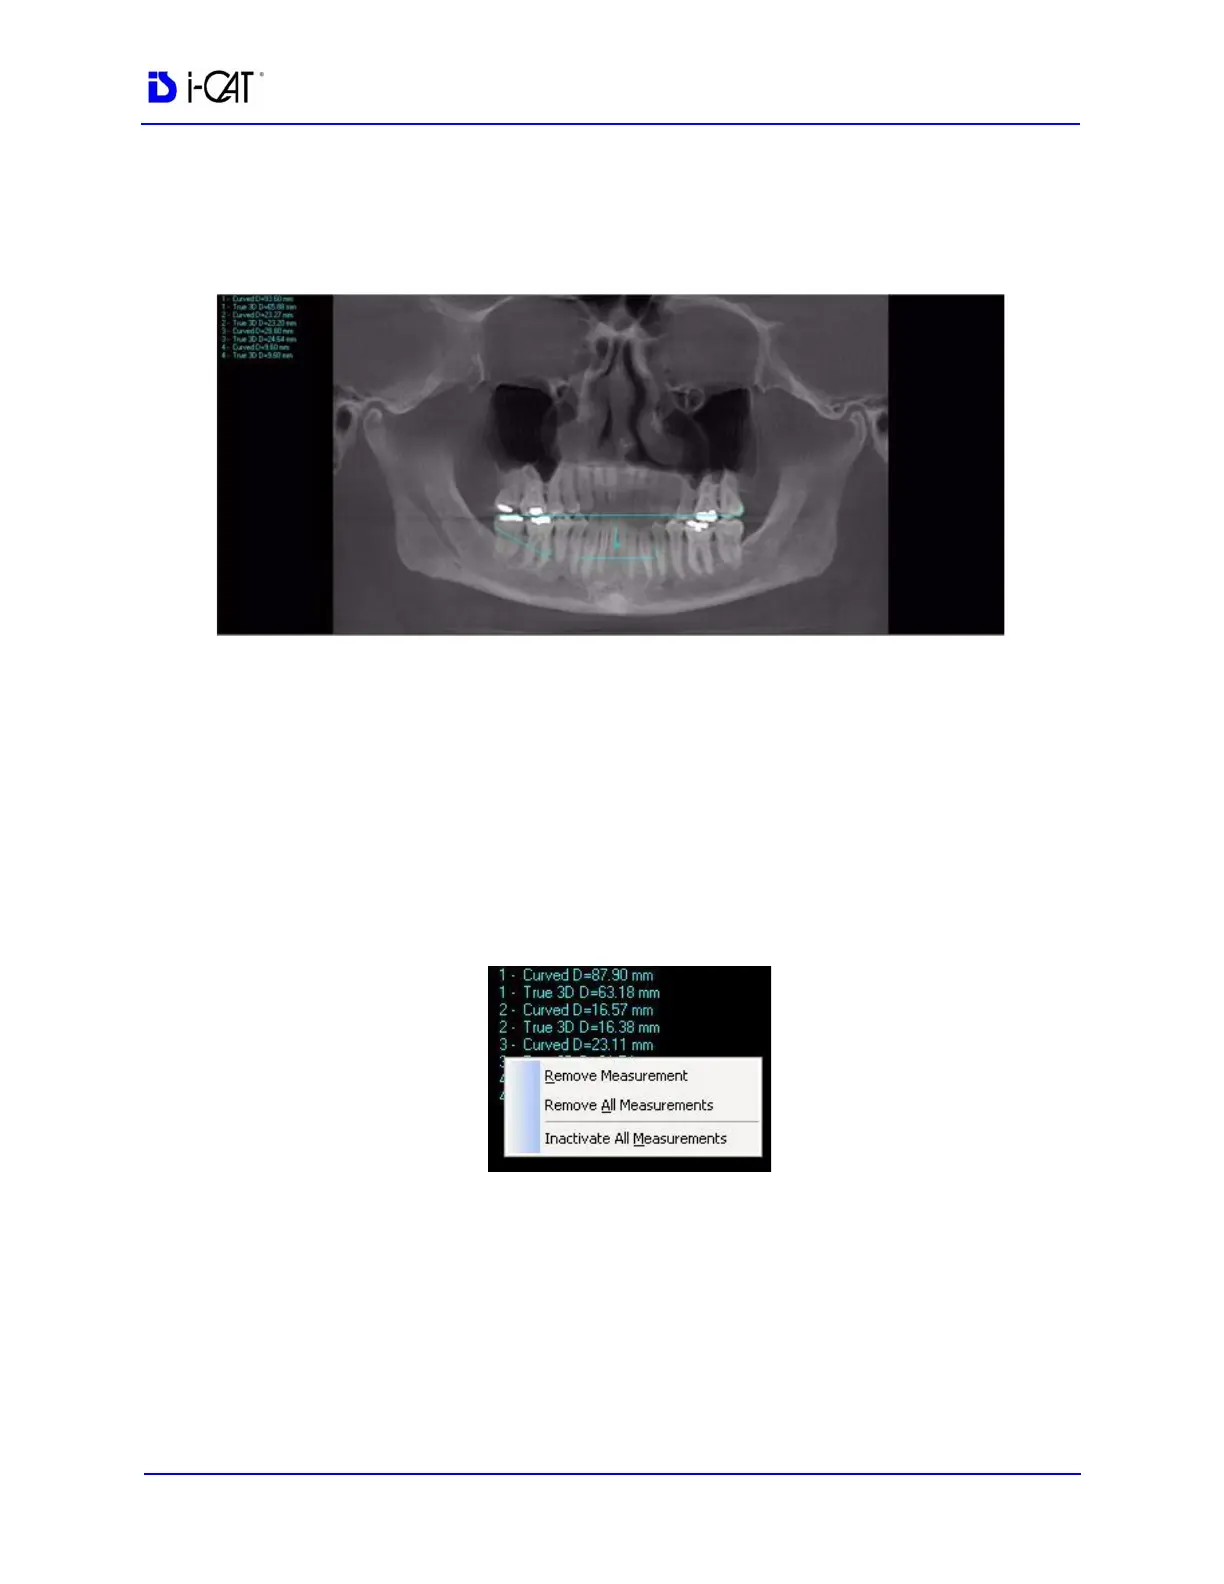

3. Repeat steps 2 and 3 to take additional measurements. A

maximum of nine distance measurements can be taken at a time

in a normal view and four in a cross section view.

To remove a specific measurement:

Measurements can be selectively removed from a view as desired. All

measurements can also be deactivated/reactivated for a view.

1. Right-click the measurement to be removed and select Remove

Measurement.

Remove All Measurements - removes all measurements from

selected view.

Inactivate All Measurements - grays out all measurement

indicators and removes the measurements from the selected

view. When this is done, the Reactivate All Measurements

becomes available.

Reactivate All Measurements - restores all of the inactivated

measurements to the selected view.